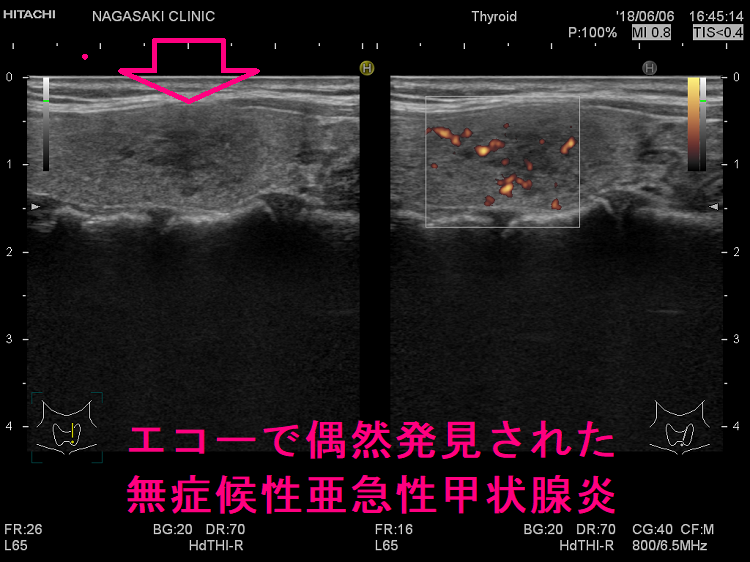

エコーで偶然発見された無症状の亜急性甲状腺炎 超音波(エコー)画像

こんな事が現実にあるのか?と首をひねるケースが時々あります[長崎甲状腺クリニック(大阪)では数年に1回程]。投薬の必要ない甲状腺機能正常橋本病の年次フォローアップ、甲状腺の病気を持つ家族がいるので自分も調べて欲しいなど、亜急性甲状腺炎とは無関係の件で甲状腺超音波(エコー)検査を行うと、偶然、亜急性甲状腺炎らしき低エコー領域が見つかることがあります。低エコー領域は痛みも発熱もなく、1-2か月後には消えてしまいます。

写真で分かる通り低エコー領域が不規則な形で、明らかに無痛性甲状腺炎の炎症巣とは異なります。甲状腺機能も正常で、一般的な項目に異常はありません。